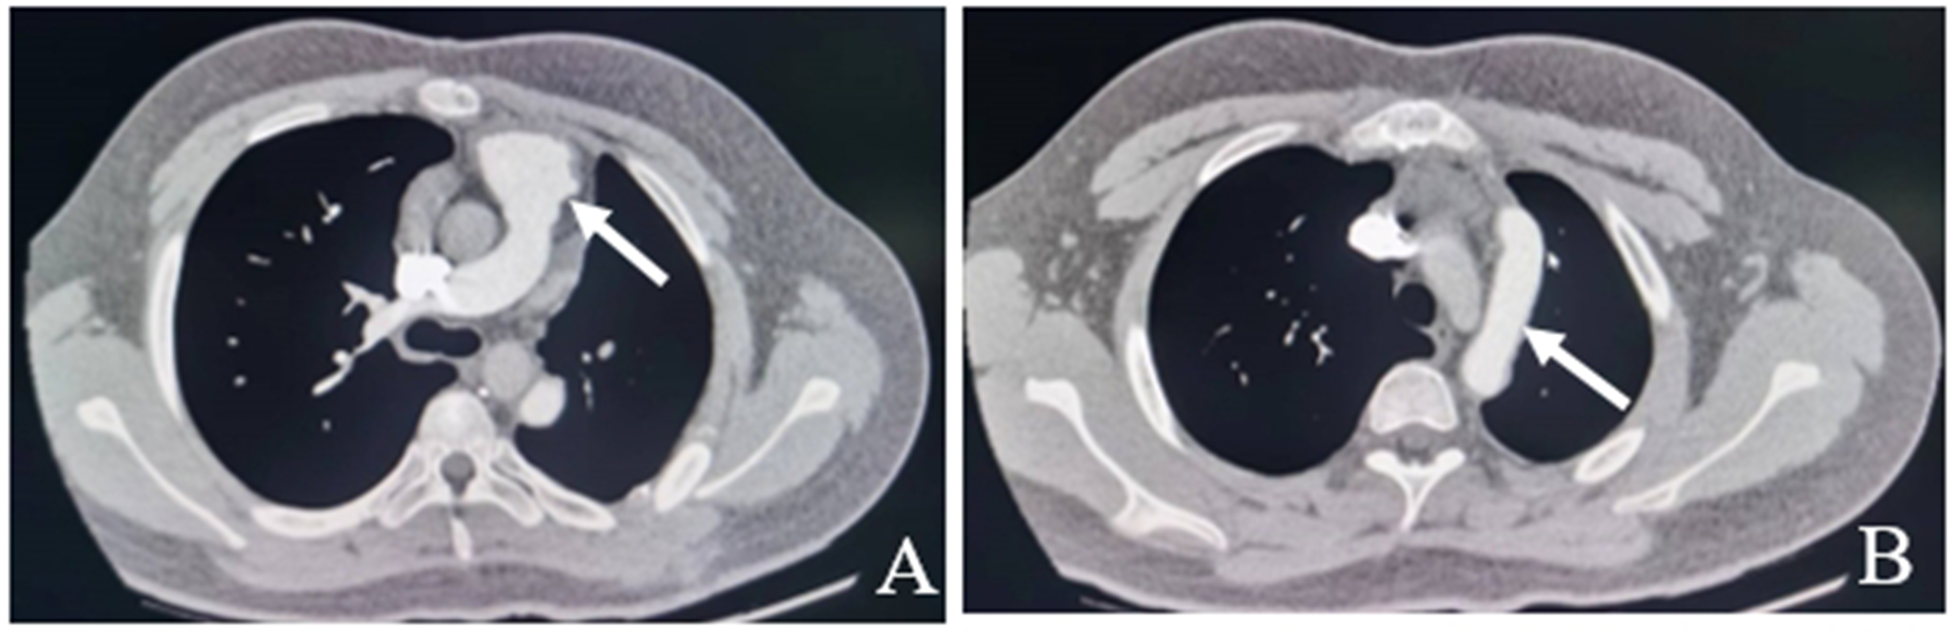

Following the surgery, the patient was moved back to the intensive care unit (ICU). The patient had stable hemodynamics and was weaned from the ventilator 6 h after the surgery, with endotracheal tube being removed. The patient was then transferred from the ICU to the cardiac surgery ward where he received anticoagulation therapy with warfarin, which was continuously adjusted according to the international normalized ratio (INR). A repeat pulmonary artery CT six months after the operation showed that the left pulmonary artery was well visualized without any obvious stenosis, dilatation, or filling defect (Figure 3).

Figure 3. Pulmonary artery CT six months after the operation show the left pulmonary artery is well visualized without any obvious stenosis, dilatation, or filling defect (white arrow). A: No stenosis at the origin of the left pulmonary artery. B: No filling defects in artificial blood vessels.

Echocardiography and CTA for the aorta and pulmonary artery are important methods to confirm the diagnosis of AOPA, and they are also helpful in identifying the anatomical characteristics and assessing the severity. Once the diagnosis is confirmed, prompt surgical treatment is recommended in order to restore the normal anatomical relationship of the pulmonary artery. Only in the absence of Eisenmenger syndrome caused by PH may the surgery be performed. Since AOPA is more frequent in infants or toddlers rather than in adults, the condition should be fully evaluated to develop an appropriate treatment plan. The preoperative imaging in this case of AOLPA from the descending aorta suggested difficulty in dealing with the descending aorta and the main pulmonary artery simultaneously under single incision; therefore, we performed a double-incision surgery instead. Separation of the left pulmonary artery and descending aorta was performed through the left fourth intercostal incision, followed by an extension of the left pulmonary artery using an artificial blood vessel and anastomosis with the main pulmonary artery through a midline incision. Postoperative re-examination indicated that the left pulmonary artery blood flow was smooth, the main pulmonary artery was in a good position, and there was no evidence of pulmonary artery stenosis or thrombosis.